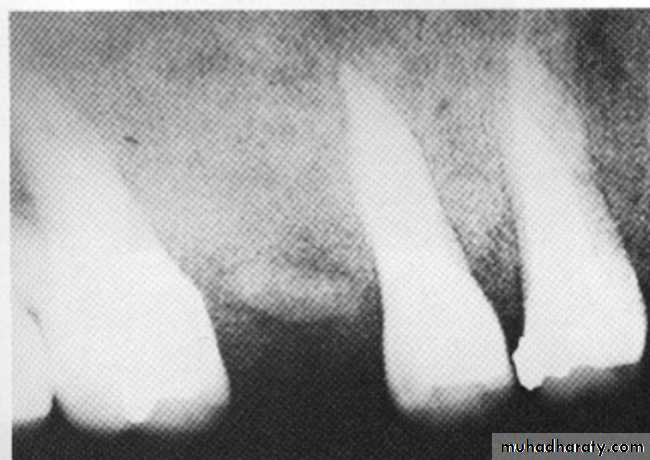

Radiographic features:

Location: Apex of involved tooth / Cervically up the tooth root.Periphery: Ill defined / Well defined, with gradual blending of normal trabecular pattern into sclerotic pattern.

Internal structure: *Early lesion→ no radiographic change.

*Widening of PDL space at the apex.

*A mixture of sclerosis (radiopaque) and rarefaction (radiolucent).

* ↑se bone formation → periapical sclerosing osteitis.

*↑se bone resorption → periapical rarefying osteitis.

Effects on surrounding structures:

* Losing of lamina dura at the apex.* Regions of sclerotic bone around apex.

* External apical root resorption.

* Inflammatory periosteal reaction (new bone formation in max. S.) → halo shadow.